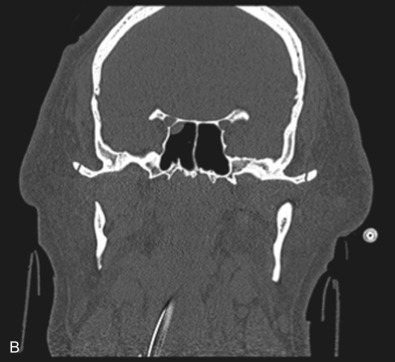

Le Fort I pattern fractures are characterized by a transverse fracture extending from the pyriform aperture, propagating laterally across the maxillary wall involving medial, anterior, and lateral components, and ending posteriorly at, or through, the level of the pterygoid plates ( Figs. 1.13.11–1.13.13 ). This results in mobilization of the lower third of the midface, whilst the upper two-thirds remains intact. The force is typically delivered above the maxillary teeth, causing a palatal/alveolar separation from the upper maxilla.